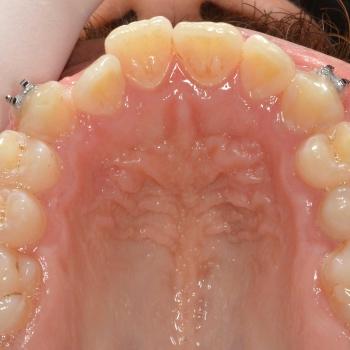

János egy másik fogorvos által befejezett, illetve később részlegesen újrakezdett fogszabályozó kezelés sikertelensége miatt keresett fel rendelőmben. Az első konzultáció alkalmával több esztétikai és funkcionális hibát is észrevettünk, többek között keresztharapást, enyhe nyitott harapást, torlódást, egyoldali Class II harapási eltérést, az alsó és felső őrlőfogak egymással nem harmonizáló dőlését, illetve az alsó középvonal funkció közbeni eltolódását balra.

A kezeléshez János hagyományos fém fogszabályozót választott, melyet kiegészítettünk a legkülönfélébb intermaxilláris gumihúzásokkal, illetve egy speciális belső oldali fogszabályozó ívvel, ami segített az alsó őrlőfogakat a nyelv irányába dönteni.

János kitartásának hála a kezelés végén tökéletes esztétikai és funkciós eredményt értünk el.